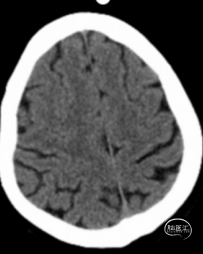

术后造影

术后24小时头颅CT:右侧基底节区少量出血及低密度灶。

术后24小时查体:神志呈清醒状态,伸舌左歪,口角向右歪斜,左侧肢体肌力4级,NIHSS评分2分。